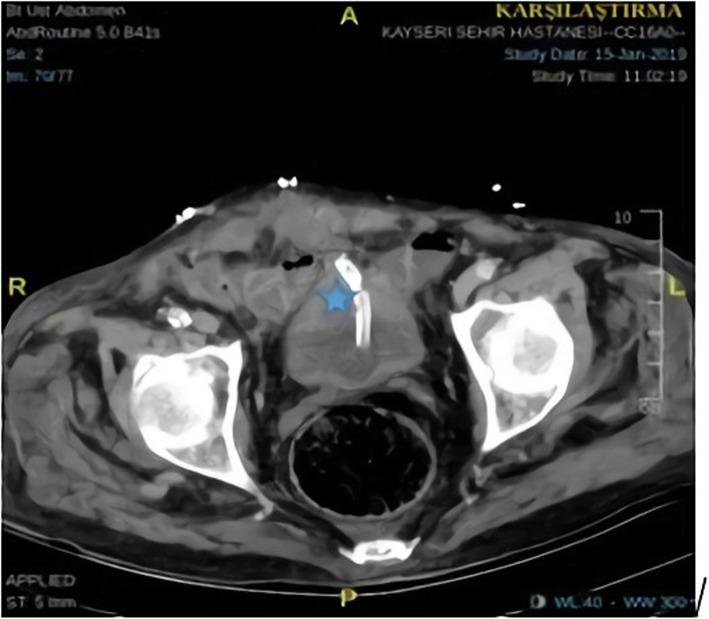

A 77-year-old Caucasian male patient was admitted to the emergency department with abdominal pain, haematuria, and a reduced volume of urine lasting for three days. The patient's amount of urine was reduced, and he came to the hospital for the first time with this complaint. The patient had local bruises on his arms and legs. From the ultrasound, retrograde cystography and computed tomography images, it was thought that there was blood accumulation due to bladder rupture to the intraperitoneal region. Spontaneous bladder rupture secondary to warfarin overdose was considered for this patient who also had an international normalized ratio (INR) level of 13.4. After the INR level was normalized with vitamin K and a prothrombin complex concentrate, the patient underwent surgery. During the operation, a catheter was placed in the bladder, and the bladder mucosa and muscle were closed separately with a primary repair performed by a urologist. The patient was discharged on the 8th postoperative day without any complications.

一名 77 岁的白人男性患者因腹痛、血尿和少尿 3 天入院到急诊科。患者的尿量减少,他第一次因这种症状来医院就诊。患者的手臂和腿部有局部瘀伤。从超声、逆行膀胱造影和计算机断层扫描图像来看,考虑到有血液积聚导致膀胱破裂到腹腔区域。考虑到患者的国际标准化比值(INR)水平为 13.4,因此认为该患者为华法林过量导致的自发性膀胱破裂。INR 水平用维生素 K 和凝血酶原复合物浓缩物正常化后,患者接受了手术。手术中,在膀胱内放置了一根导管,泌尿科医生分别对膀胱黏膜和肌肉进行了一期修复。患者在术后第 8 天没有任何并发症出院。